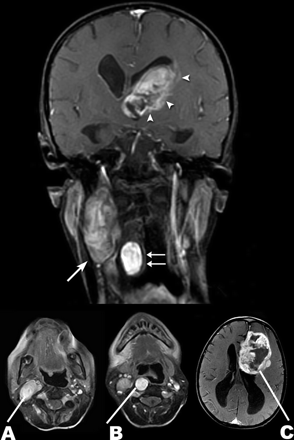

良性和恶性病理神经纤维瘤病1型

梅勒妮•沃克,帕特里克•Gabikian